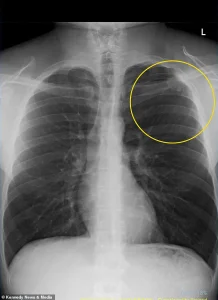

Rushed to the hospital, he was diagnosed with a partially collapsed lung, a condition known medically as a pneumothorax.

This occurs when air leaks into the chest cavity, creating pressure that forces the lung to collapse.

At the hospital, doctors found his left lung had collapsed by 10 percent—a minor collapse, but one that came with a dire warning.